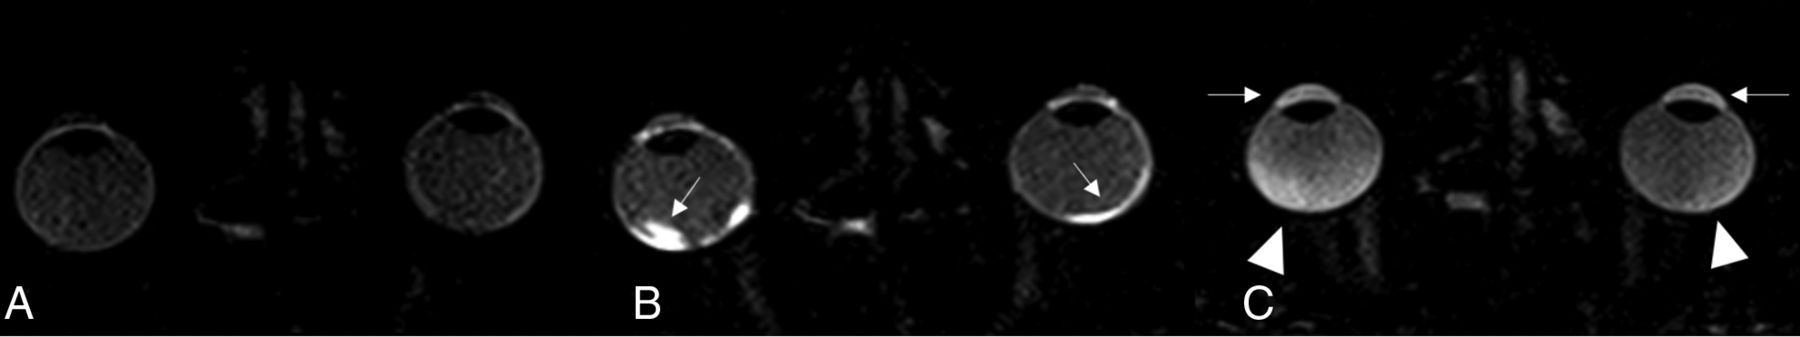

In the VB, the mean relative SI increase of 0.11 (SD, 0.20) after 20 minutes was significantly different (p20min = .02), while mean relative SI increase of 0.42 (SD, 0.49) after 120 minutes was similar (p120min = .09) to that in the control group, with mean relative SI increase of 0.04 (SD, 0.26) after 20 minutes and 0.16 (SD, 0.43) after 120 minutes (Fig 3).

Example of a patient with a disorder in the AEC on the right; native scan (A), scan 20 minutes after gadolinium injection demonstrating a higher permeability of Gd in the lateral eye chamber (small arrow) and increased Gd enhancement in the in the central eye chamber on the right (thick arrow) (B), and the VB (arrowhead) in the late scan after 120 minutes in the right eye (C).